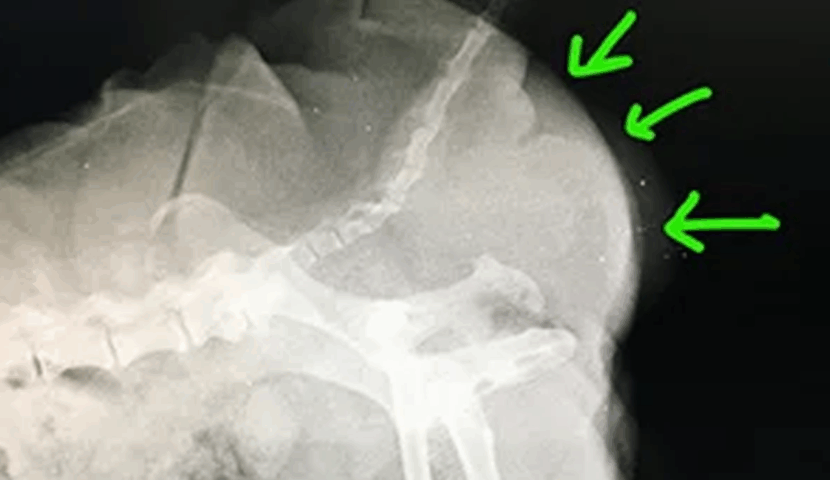

【検査内容】

・血液検査・レントゲン検査・超音波検査・直腸検査

身体検査で臀部の膨らみを確認。触診・画像検査で腸と前立腺の会陰部脱出が認められた。